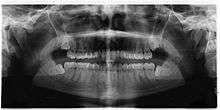

If the tooth cannot be assessed with clinical exam alone, the diagnosis is made using either a panoramic radiograph or cone-beam CT. Where unerupted wisdom teeth still have eruption potential several predictors are used to determine the chance of the teeth becoming impacted. The ratio of space between the tooth crown length and the amount of space available, the angle of the teeth compared to the other teeth are the two most commonly used predictors, with the space ratio being the most accurate. Despite the capacity for movement into early adulthood, the likelihood that the tooth will become impacted can be predicted when the ratio of space available to the length of the crown of the tooth is under 1.[3]:141

Screening

There is no standard to screen for wisdom teeth. It has been suggested, absent evidence to support routinely retaining or removing wisdom teeth, that evaluation with panoramic radiograph, starting between the ages of 16 and 25 be completed every 3 years. Once there is the possibility of the teeth developing disease, then a discussion about the operative risks versus long-term risk of retention with an oral and maxillofacial surgeon or other clinician trained to evaluate wisdom teeth is recommended. These recommendations are based on expert opinion level evidence.[17] Screening at a younger age may be required if the second molars (the "12-year molars") fail to erupt as ectopic positioning of the wisdom teeth can prevent their eruption. Radiographs can be avoided if the majority of the tooth is visible in the mouth.